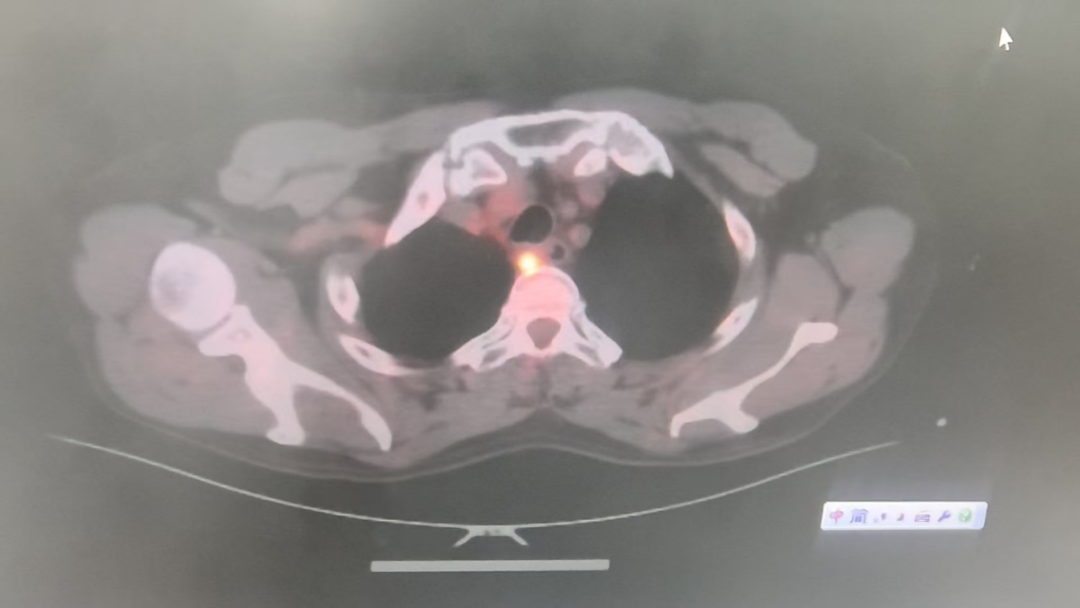

心胸外科副主任、主任医师王明智,主治医师刘炬博士团队接到会诊后,为陈阿公进行全面检查。胃镜提示:肿瘤位于食管开口处,厚11mm,突破食管外层,已经环绕食管3/4周,周围多发肿大淋巴结;CT提示:食管高位肿瘤,48mm*18mm*16mm,与支气管后壁分界不清,周围多发淋巴结;PET-CT提示:2-4胸椎水平食管上段食管癌,右下颈气管旁、右上气管旁淋巴结疑转移。综合考虑局部晚期、高位、食管恶性肿瘤,直接进行手术的风险及难度都很大,医生建议实施新辅助治疗后再进行手术。但这样的治疗方式,让家属们陷入两难境地。

△检查结果